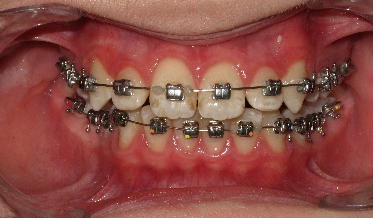

После дистализации боковых сегментов на верхней челюсти и правильной постановки клыков в зубной ряд проведена фиксация аппарата на нижний зубной ряд и дальнейшая коррекция окклюзии проводится по стандартному протоколу, т.е. нормализация формы зубных рядов на верхней и нижней челюсти с правильной постановкой зубов по торку в боковых и во фронтальном отделах, что дает реализация программы, заложенная в пассивной самолигирующей брекет- системе NexStep Pro 0.22. (рис.8)

Рис.8. Этап контроля торка на верхней челюсти и фиксация аппарата на нижней челюсти для проведения этапа нивелирования.